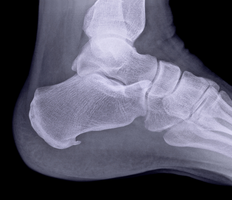

In order to diagnose a heel spur, any pain will first be discussed during a consultation. The consultant will usually then examine the foot to check whether any pain is triggered by pressure, and if so, in which areas. If the heel spur is particularly large, the consultant might be able to feel it. To make a definitive diagnosis, a heel spur can be detected via X-ray. Here, it will be visible as a bone spur in the shape of a thorn.